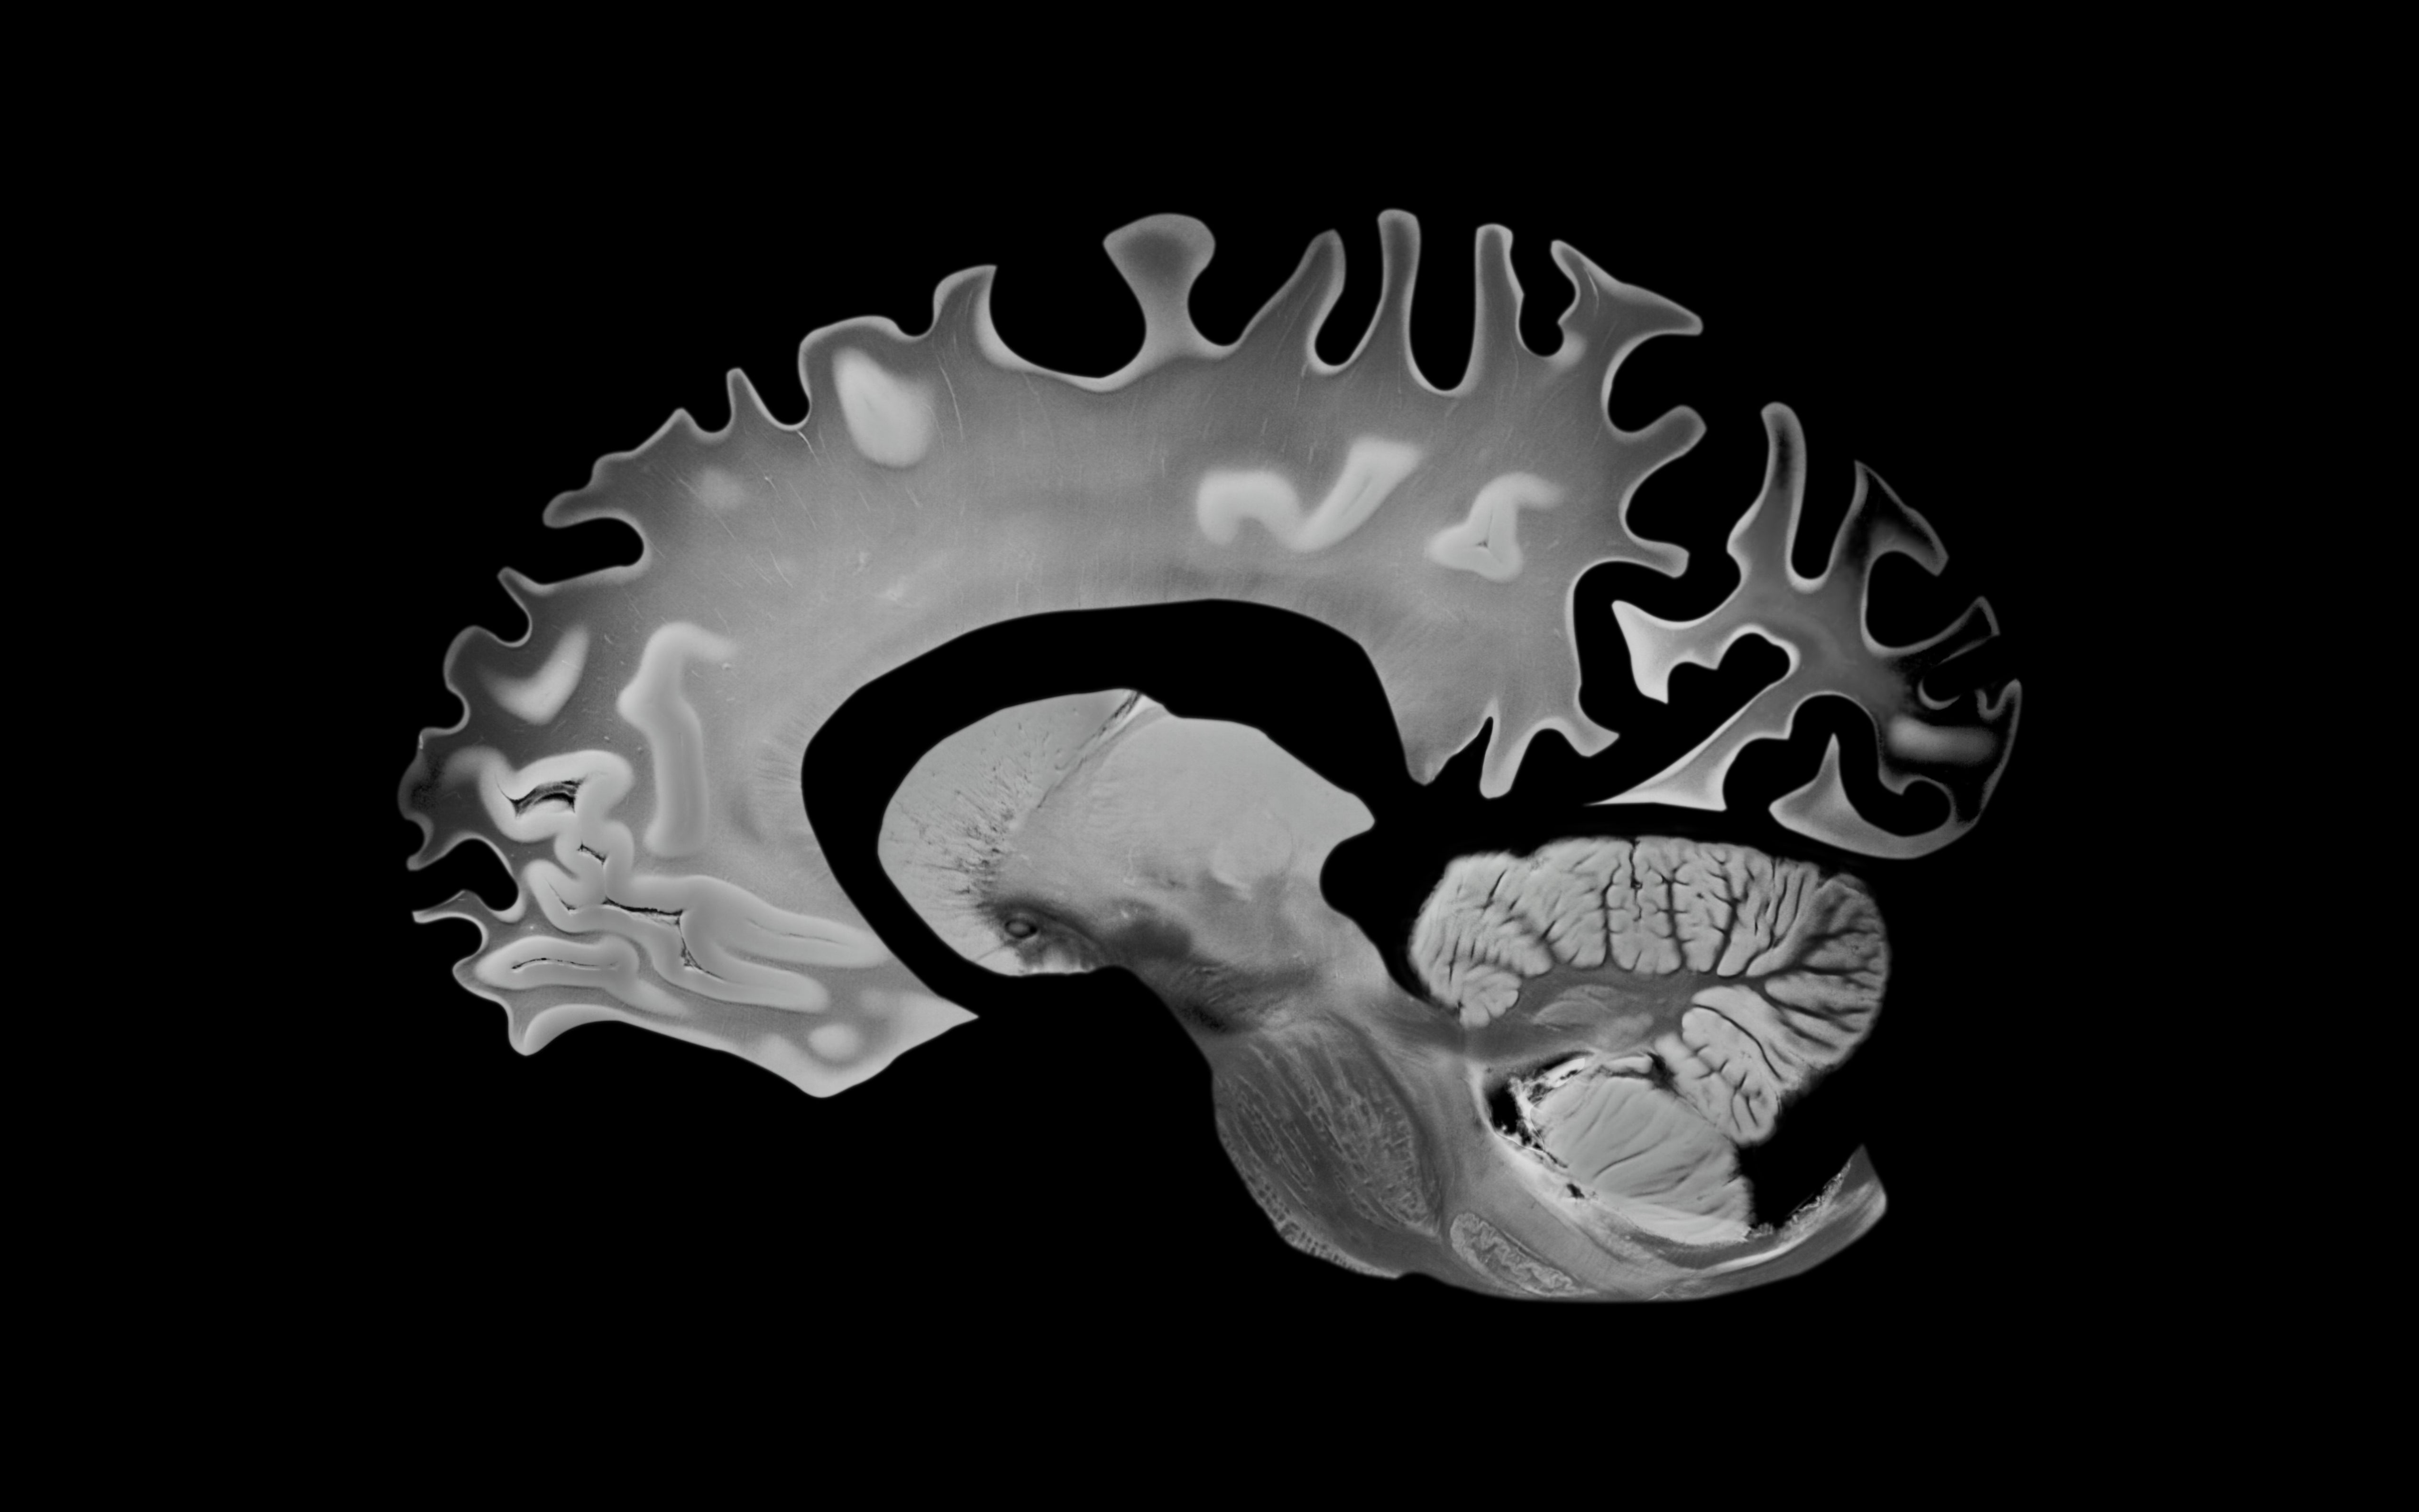

Your encephalon has a web called the glymphatic strategy that clears toxins portion you sleep. These toxins see amyloid beta, a macromolecule that builds up successful the encephalon arsenic dementia develops. So if you are experiencing slumber disturbances that importantly change your sleep-wake cycle, your assemblage could beryllium giving you an aboriginal informing sign.